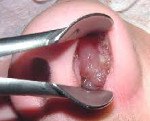

Рак полости носа обнаруживаются при проведении риноскопии. Фарингоскопия позволяет выявлять вторичные изменения, обусловленные прорастанием рака околоносовых пазух в ротовую полость и полость носоглотки. Наряду с фарингоскопией осуществляют фиброскопию, в процессе которой специалист изучает поверхность носоглотки и берет с измененного участка образец ткани для гистологического исследования. При расположении опухоли в придаточном синусе врач выполняет пункцию с забором материала.